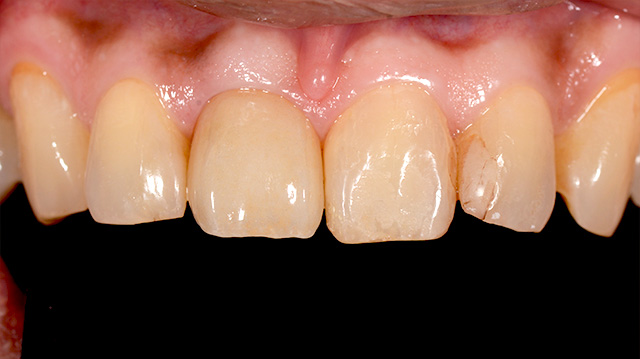

| 年代・性別 | 50代 男性 |

|---|---|

| 主訴 | 前歯を綺麗にしたい |

| 治療回数 | 3回 |

| 治療期間 | 約1ヶ月 |

| 費用 | 仮歯 5,500円 ジルコニアクラウン 176,000円 |

*キャンセルポリシーをご一読のうえご予約ください